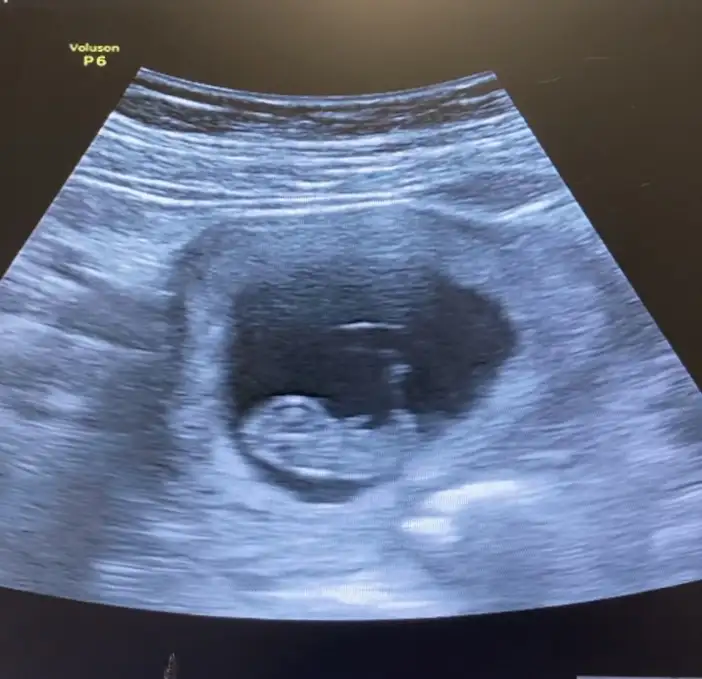

merhaba Pasha22 Pasha22 :KK200: 9+3 kontrolümüzden, cinsiyet tahmini yapabilir misin:)

• IMG_2856.webp

IMG_2856.webp

22,2 KB · Görüntüleme: 64